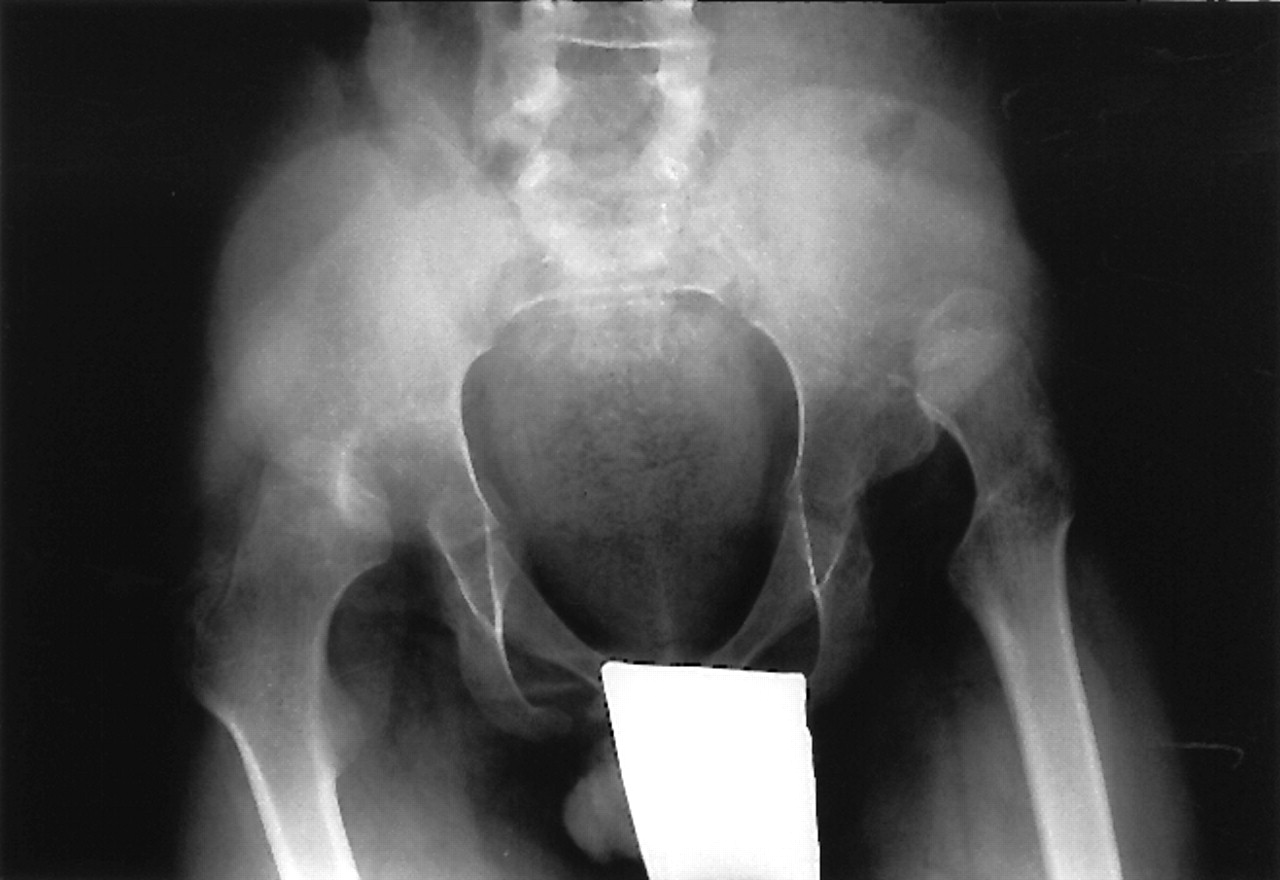

Cranial placement of the acetabular cup for hip dysplasia. Download Hip Dysplasia Orthobullets learn how to perform a comprehensive hip physical exam on adult patients, including inspection, palpation, neurovascular, rom, and. a review article on the epidemiology, pathomechanism, diagnosis, and treatment of hip dysplasia in adults. learn about the causes, presentation, diagnosis and treatment of ddh, a spectrum of conditions characterized by varying displacement of. learn about the epidemiology,. Hip Dysplasia Orthobullets.